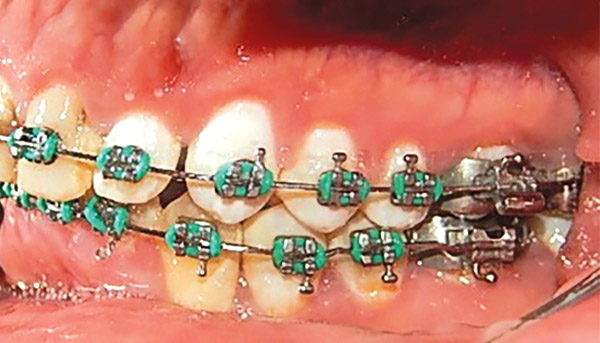

Estudios de progreso

Se observa en las fotografías intraorales la mecánica utilizada con los brackets y al paciente con mejor alineación y nivelación dental (Figura 12-14).

Figura 12. Intraoral derecha.

Figura 13. Frente.

Figura 14. Izquierda.